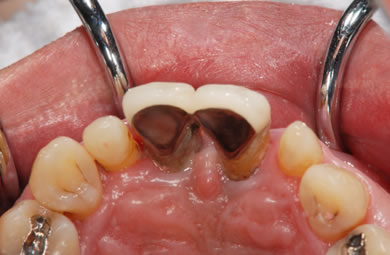

インプラントの症例写真 IMPLANT

骨再生スピードインプラント治療+セラミック治療

| 主訴 | 上の前歯が6ヶ月程前からぐらつき出した。 | ||||||||||||||||||||||||||||||||

| 治療方針 | 審美的・機能的回復をなるべく早くはかる為、抜歯と同時にインプラント治療を行う。また、奥歯に関しては歯周病が進行しているものの、歯の保存が可能な状態である為、エムドゲインを使用し、組織再生をはかる。 | ||||||||||||||||||||||||||||||||

| 治療内容 | インプラント3本(抜歯即日スピードインプラント+GBR)、ハイブリッドセラミック4本、オールセラミックラミネートベニア2本、エムゲドイン組織再生療法 | ||||||||||||||||||||||||||||||||